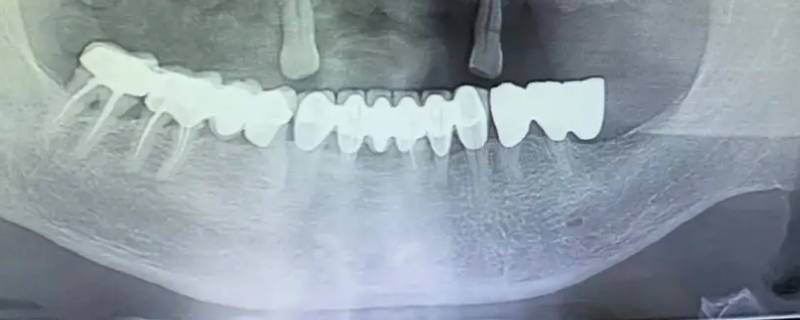

最佳答案在全景片显影中,骨骼、牙齿、补牙材料、牙冠这种组织属于高密度组织,在影像上呈现白色;像牙龈和牙髓这一类组织属于低密度组织,低厚度组织,会呈黑色或灰色。蛀牙在全景片显影上会出现黑色阴影的缺损,如果是邻面龋以及龋坏程度,通常需要到医院,医生用探针、口镜等进行确定。